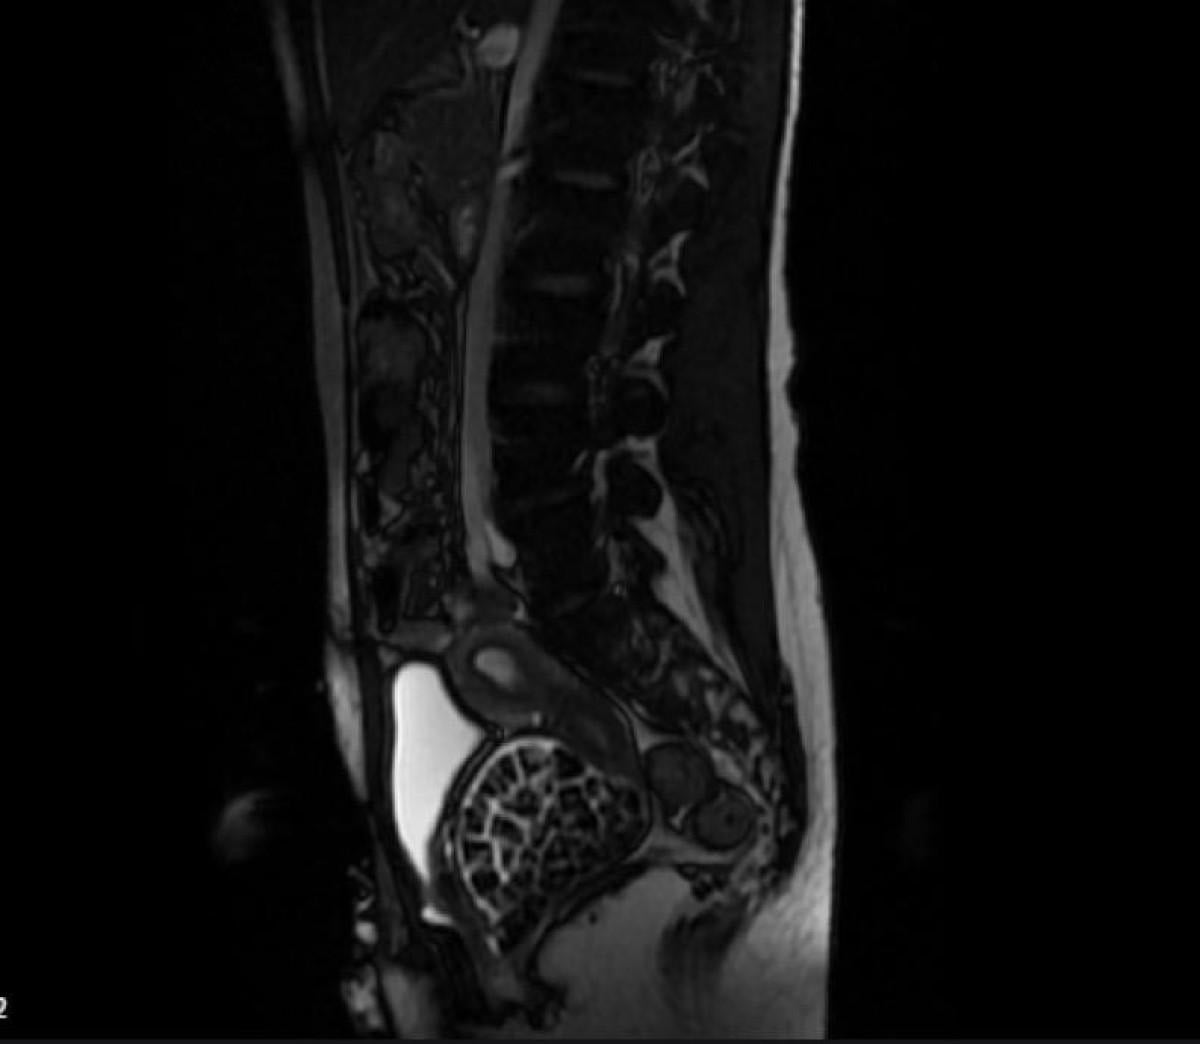

Hastasının durumuna yönelik konuşan Üroloji Uzmanı Doç. Dr. Erkan Erkan, "Hastamızın 2004 yılında doğduğunu ardından doğar doğmaz ekstrofi vezika dediğimiz 50 binde bir görülen bir anomaliden dolayı art arda ameliyatlar geçirdiğini öğrendik. 10 yaşında yine bir ameliyat geçirmişti, gerekli görüntüleme ve tetkiklerimizi yaptırdık. Normalde mesanesinin olması gereken yerin hemen arka kısmında taşlarla dolu bir kese olduğunu gördük, bunun üzerine ek görüntülemeler; MR çektirdik. Hastamız çelişkili açıklamalar almıştı, kendi radyolojik kliniğimiz ve edindiğimiz konsültasyonlarda taşların mesanede değil vajinal boşlukta oluştuğunu düşündük, bir planlama yaptık.

Kadın doğum hocamızın da çabasıyla taşları tamamen temizledik ardından ileride normal bir hayat sürmesi bakımından oraya plastik cerrahi yaptık. 287 adet taş çıkardık, pratikte gerçekten görünce çok şaşırdık çünkü bu aynı zamanda literatürde çok nadir görülen bir olay. Biz ameliyata hazırlanırken de teorik olarak biraz araştırdık. Literatürde gördüğümüz kadarıyla buna benzer bu tanıma uyan bir vaka vardı. Literatürde sanırım yayınlanmış 2’nci vaka olacak. Farkındalık çok önemli, bilinçli bir hastamız vardı. Doğumsal anomaliyle doğan çocuklarımızda ileride bunlara bağlı bazı sıkıntılar çıkabileceğinin öngörülmesi lazım. İlgili tedavilerini alsalar bile düzenli takiplere gelmeleri gerekiyor. İleride eğer dikkat etmezse ki zannetmiyorum, tekrarlayabilir. Bu rahatsızlık ekstrofi vezikal epispadias durumu, çok nadir bir durum." dedi.

Genç kızın uzun süredir devam eden karın ağrısı olduğunu söyleyerek sözlerine başlayan Jinekolojik Onkoloji Uzmanı Op. Dr. Emin Erhan Dönmez, "Mesane taşları olduğu düşünülerek daha büyük bir hastaneye refere edilmiş. Aramızda mini bir konsey yaparak muayene ettik. Vajen bir hazne görevi görerek orada durağan bir idrar, uzun süre beklediği için idrar içindeki minerallerde çökerek taşlar oluşmuş. Mesanedeki idrarın vajene akmış olabileceği ve vajende göllenen idrar nedeniyle taşların burada oluşacağını düşündük, ameliyatımızı planladık. Ameliyata tanı amaçlı girmiştik, sistoskopi (Mesane gibi idrar yollarını kapsayan kısımlardaki rahatsızlıkların teşhis ve tedavisinde kullanılan endoskopik bir yöntem) dediğimiz ameliyatı Erkan Hocam ile birlikte gerçekleştirdik.

Önce mesaneyi bir görüntüledik, mesane tabanına yaklaşık 2-3 cm’lik bir alandan vajene fistülize olduğunu gördük. Mesaneden vajene geçtiğimiz esnada tüm vajenin taşlarla dolu olduğunu gördük. Tanı amacıyla girdiğimiz ameliyatta her şey de olağan gittiği için tedaviye geçtik. Taşların çıkabileceği kadar bir genişlik sağladık. Daha sonra yaklaşık en büyüğü 2,5 cm boyutlarında olan, irili ufaklı 287 tane taşı ameliyat esnasında çıkarmış olduk. Taşların tekrarlamaması için idrarın göllenmemesi, en azından dışarıya rahatça boşalabilmesi için vajinal rekonstrüksiyonu sağladık. Ameliyatta da herhangi bir problem yaşamadık. Literatürü Erkan Hocam ile birlikte değerlendirmiştik. Primer olarak vajende birikmiş olan bu kadar çok sayıda taşla ilgili bir makale görmedik, rastlamadık." dedi.